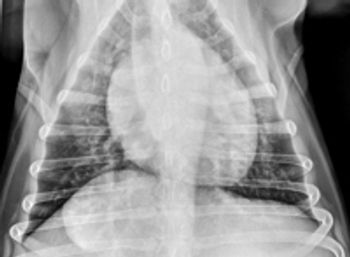

Thoracic radiographs for metastatic disease are part of every day practice. A diagnosis of pulmonary nodules has an important effect on treatment decisions, and some radiographs are difficult to interpret.